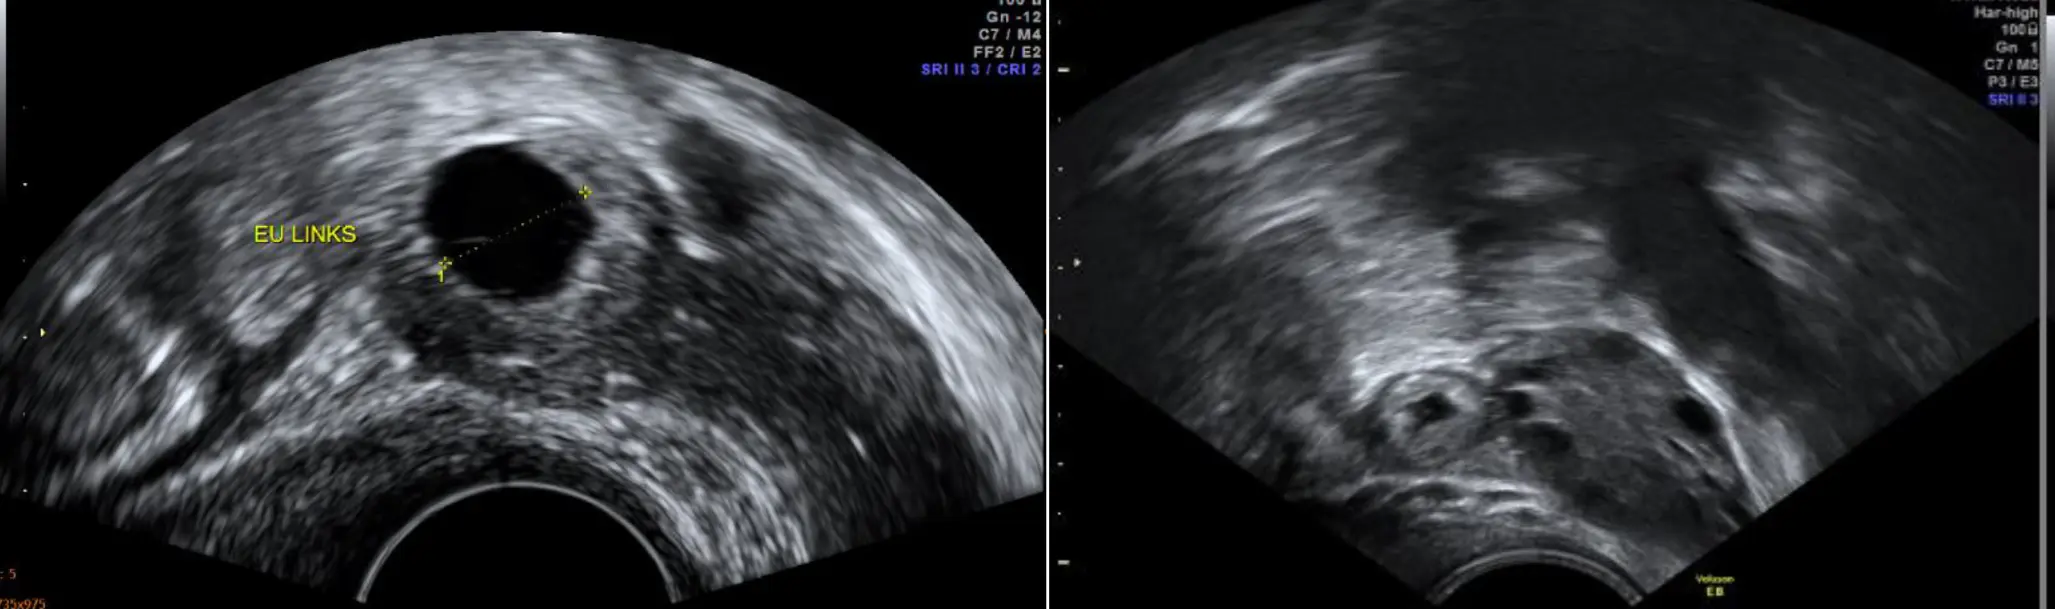

- Ultraschalluntersuchung : Ein Ultraschall kann helfen, die Lage des Embryos zu identifizieren und eine Schwangerschaft in der Gebärmutter auszuschließen.